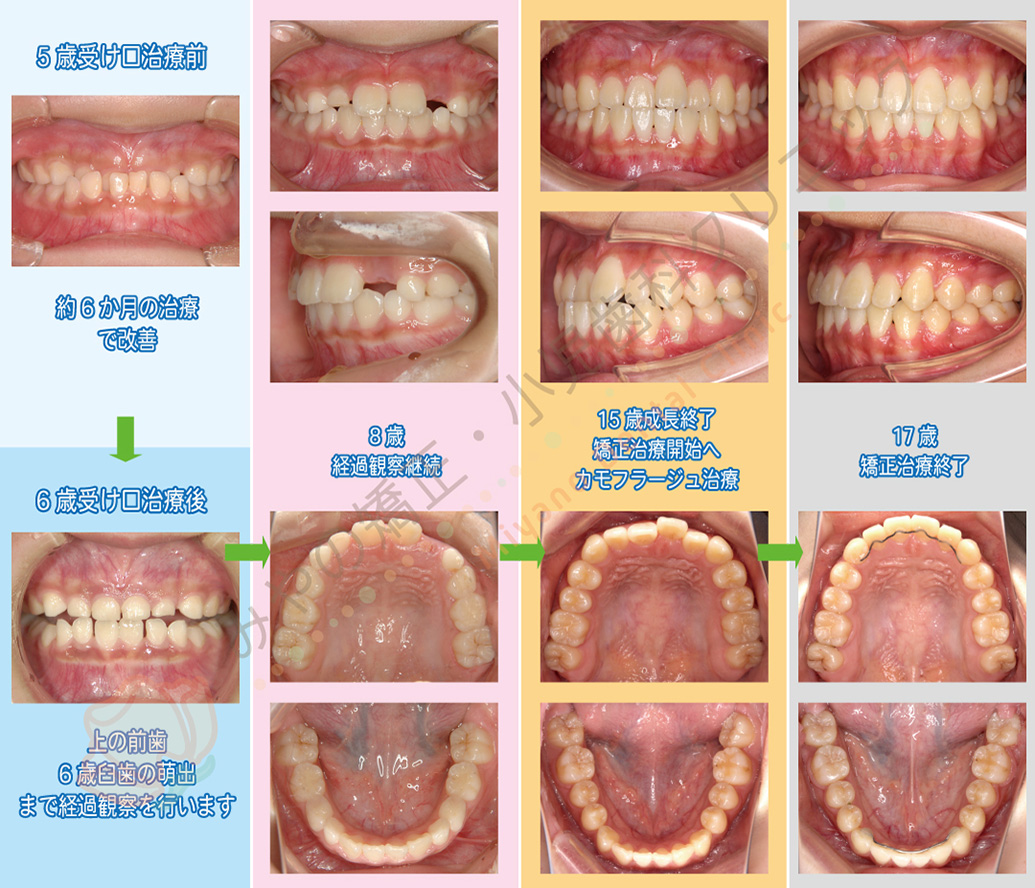

受け口が主訴で来院され、5歳で受け口治療を行った後の治療経過の例です。

乳歯列の受け口は約6か月で改善しました。乳歯列の時点で一旦受け口は改善しましたが、下顎の成長が良いタイプであったため身長が伸びるとともに下顎がさらに前方成長し受け口が顕著になる可能性が高いと判断し、1期治療や2期治療は戦略的に行わず身長の伸びが止まるまで待機していた患者様です。(顕著なスペース不足など受け口以外の問題が少なかったため何もしない方が良いと判断しています)

骨格的な受け口タイプの場合、受け口顔貌を改善したい場合は外科矯正治療の適用となります。

骨格は受け口の状態ですが、手術は避け歯の角度を調整してかみ合わせのみ改善する方法をカモフラージュ治療といいます。

これらの選択は実は矯正歯科医が決定するというよりも、患者様の希望がどちらかにより診断が変わるというのが適切な表現です。

ですので、「当院であれば手術はしなくて矯正治療が可能です」というのは矯正医の主観でしかなく、患者様の希望が顔貌の改善であるならば外科矯正を選択するべきケースも多いです。

この症例の患者様は15歳になり身長が止まった段階で、外科矯正かカモフラージュ治療か相談しインプラントアンカーを使用したワイヤー矯正によるカモフラージュ治療を選択されました。最初の矯正治療開始から矯正終了まで12年の年月を要しています。成長による変化はありませんが、舌や口唇の習癖によって今後も歯並びが変化する可能性があるため、リテーナーの使用も重要となります。治療費用はトータル約120万円となりました。